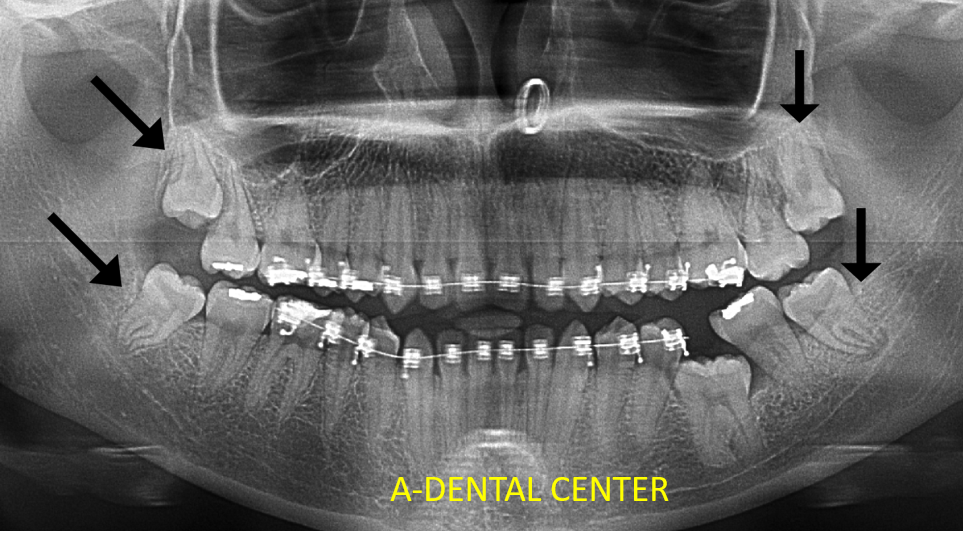

Dental X-rays in North Hollywood reveal what clinical examination simply cannot. They show several critical things that would otherwise go completely undetected:

- Cavities forming between teeth or under existing restorations — completely invisible to the naked eye until they have grown large enough to require complex treatment. Our post on what happens if you don’t fill a cavity explains exactly how fast untreated decay progresses once it goes undetected.

- Bone loss from gum disease — occurring below the visible gum line. This is directly connected to gum recession that patients often do not notice until significant damage has already occurred.

- Impacted, unerupted, or problematic wisdom teeth — often completely asymptomatic until they cause damage to adjacent teeth

- Infections or cysts at the root tips of teeth — detectable only through imaging

- Root fractures and other structural issues — frequently missed without X-ray confirmation

Full-mouth X-rays or a panoramic X-ray are typically taken at the first visit regardless of risk level — to establish a baseline and identify anything requiring attention. This is one reason your first appointment after years away will include a full X-ray series.